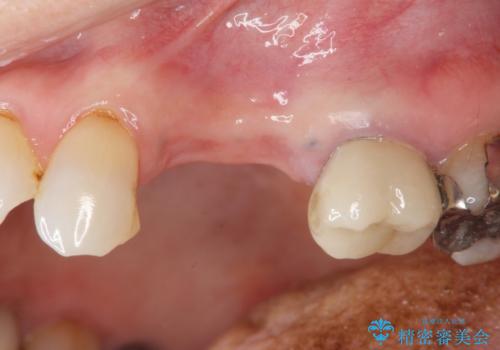

抜去後の補綴治療は長いブリッジではなくインプラント治療を希望されましたが、穿孔・破折による周囲の骨吸収をリカバリーすべく骨の造成を伴うインプラント治療を計画します。

今回はが原因で失われてしまった骨の幅を回復することで長期的な予後を見込めるインプラント治療を行うことができました。